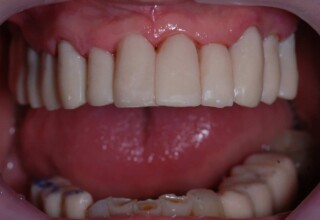

Full mouth prosthetic reconstruction on implants with a different approach on upper and lower jaw

Lower jaw: extractions, direct implant placement and immediate loading (same day) with a transitional bridge.

Upper jaw: Sequential extractions, sequential implant placement and gradual incorporation in the temporary bridge so that the patient was never left without fixed teeth. The aim of the above approach was to have the patient in continuous functional and aesthetic reconstruction, without immediate loading due to anatomical restrictions. Old smiling photos of the patient were used because the natural shape of the teeth was completely lost due to repetitive prosthetic attempts. Tooth relationship and teeth-lip support was transferred to the temporary restorations. Two different transitional bridges were needed to fully estimate phonetics, mastication and esthetics. After the necessary adjustments were finalized, the temporary bridge was used as a guide for the permanent bridges.

Initial

Intermediate

Final